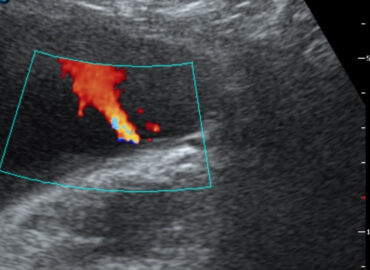

46 años. Control ginecológico